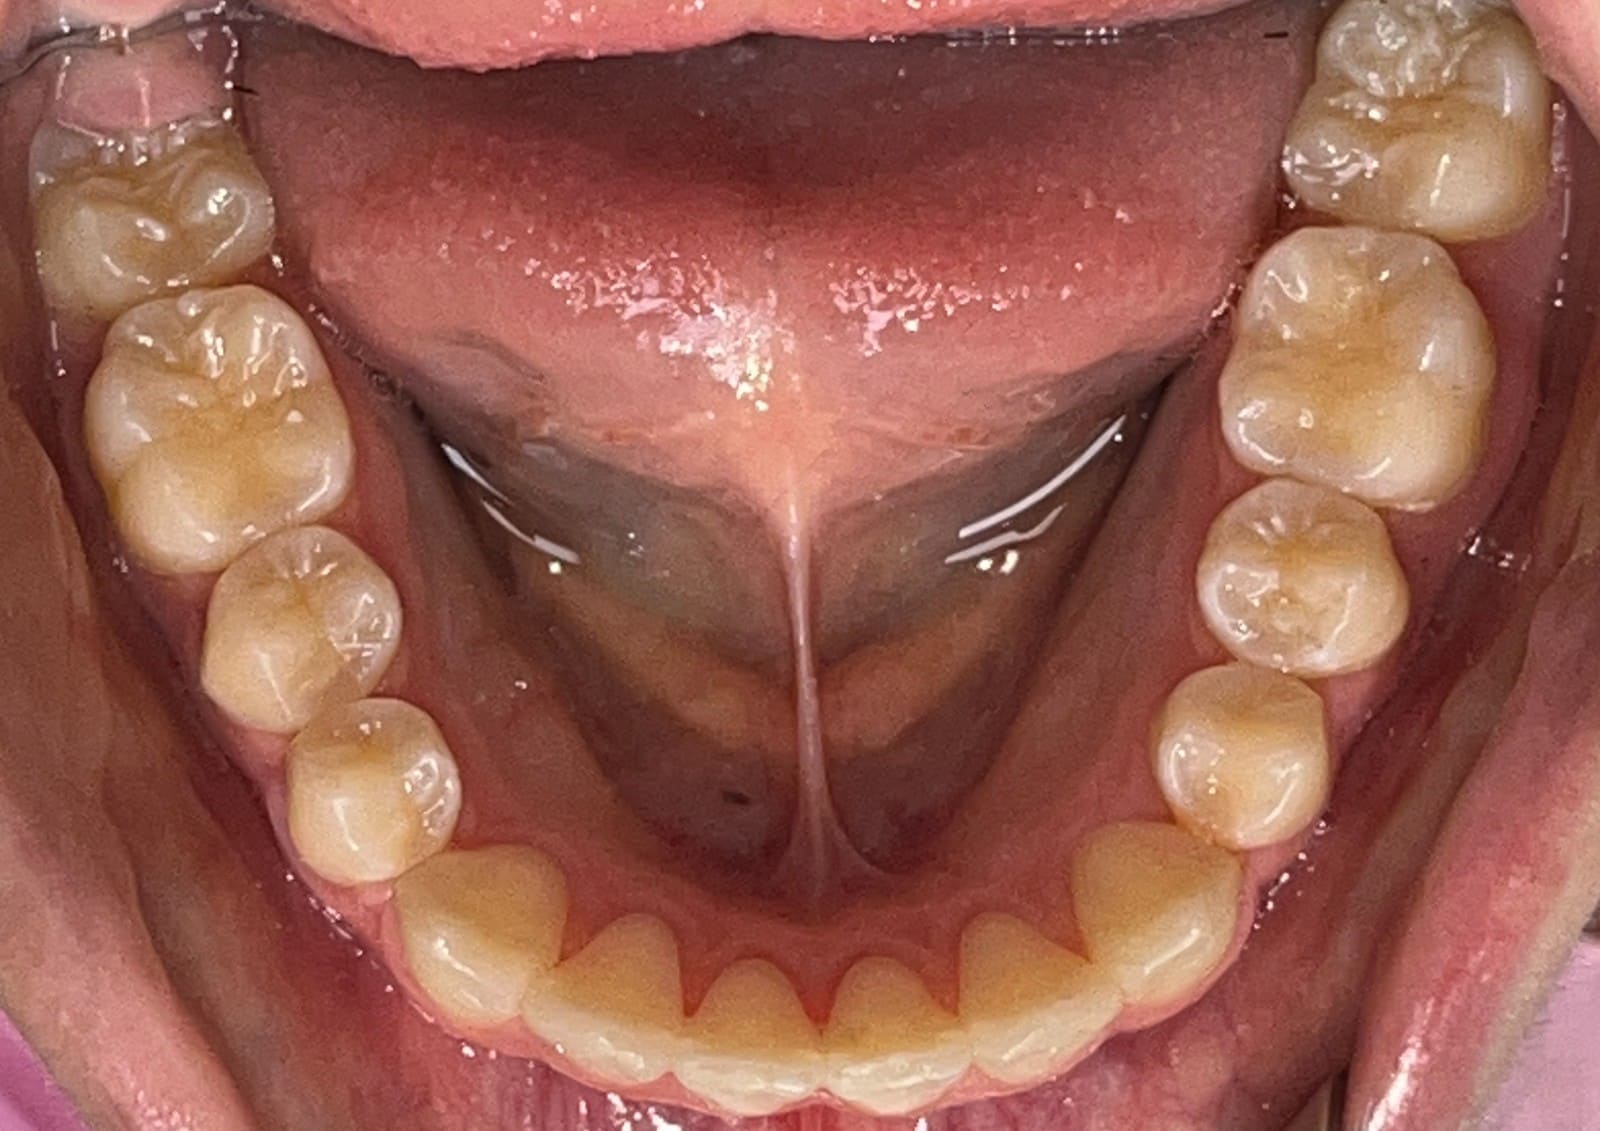

Final

Results achieved

- Class I relationship achieved

- Functional canine guidance on both sides

- Normal overjet and overbite achieved

- Deepbite improved

- Overjet improved

- Midlines coincident

- Curve of Spee leveled

- Arches aligned and coordinated

- Aesthetic smile line was achieved

- All treatment goals were achieved case